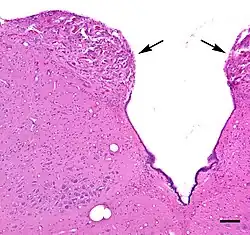

The area postrema is a paired protuberance found at the inferoposterior limit of the fourth ventricle.[1][5] Specialized ependymal cells are found within the area postrema. These cells differ slightly from the majority of ependymal cells (ependymocytes), forming a unicellular epithelial lining of the ventricles and central canal. The area postrema is separated from the vagal trigone by the funiculus separans, a thin semitransparent ridge.[1][5] The vagal trigone overlies the dorsal vagal nucleus and is situated on the caudal end of the rhomboid fossa or 'floor' of the fourth ventricle. The area postrema is situated just before the obex, the inferior apex of the caudal ventricular floor. Both the funiculus separans and area postrema have a similar thick ependyma-containing tanycyte covering. Ependyma and tanycytes can participate in the transport of neurochemicals into and out of the cerebrospinal fluid from its cells or adjacent neurons, glia or vessels. Ependyma and tanycytes may also participate in chemoreception.[1][5]

The area postrema is considered a circumventricular organ because of its proximity to the ventricular system.[2] In a morphological study, area postrema capillaries in the ventral subregion of area postrema were shown to be relatively impermeable like those of the brain, whereas medial and dorsal area postrema capillaries had microscopic characteristics of high permeability, a characteristic called sinusoidal.[6] Subregional capillary density of the area postrema was highest near the ventricular interface, and was nearly twice as dense as the capillary densities of the adjacent solitary nucleus (SN), and dorsal motor nucleus of the vagus nerve.[6] A tanycyte barrier partially compensates for high capillary permeability in the area postrema.[7]